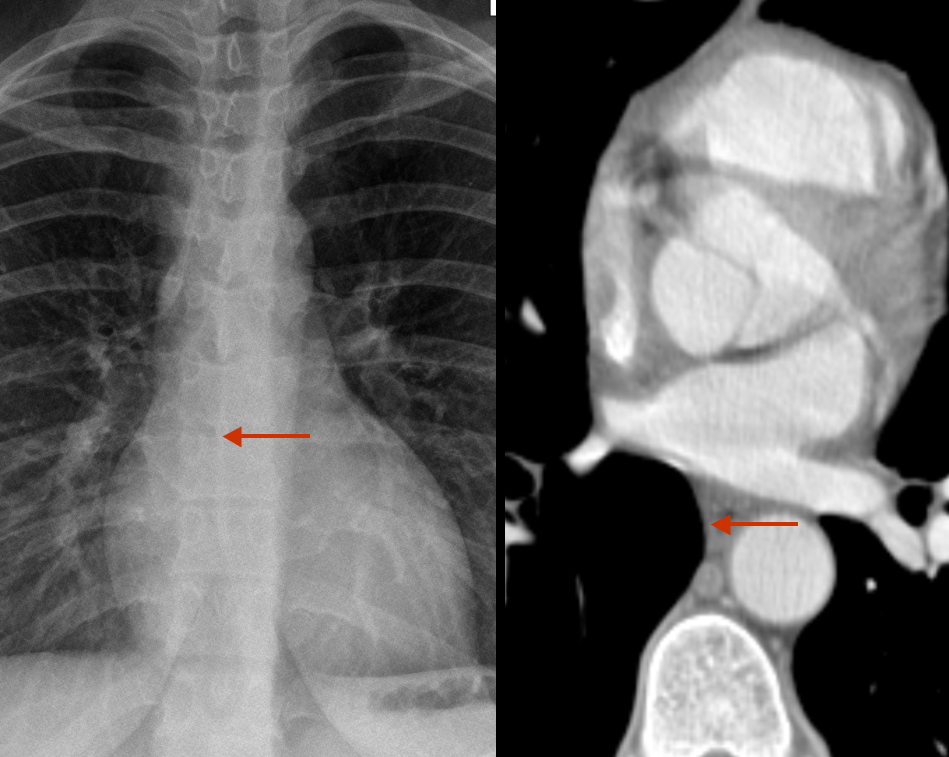

AE interface b)